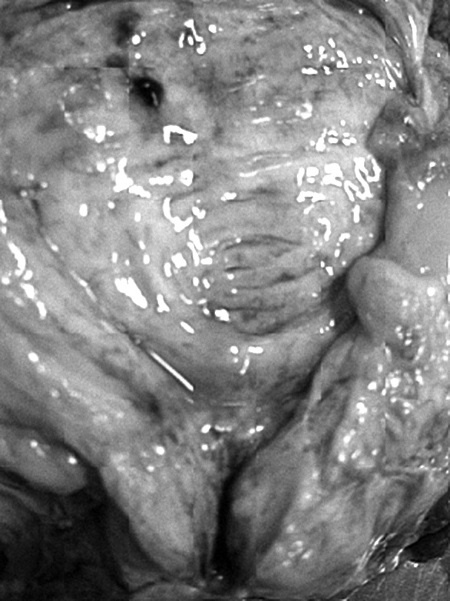

Постинфарктный кардиосклероз

Иллюстрация к книге — Маломобильный пациент [i_003.jpg]